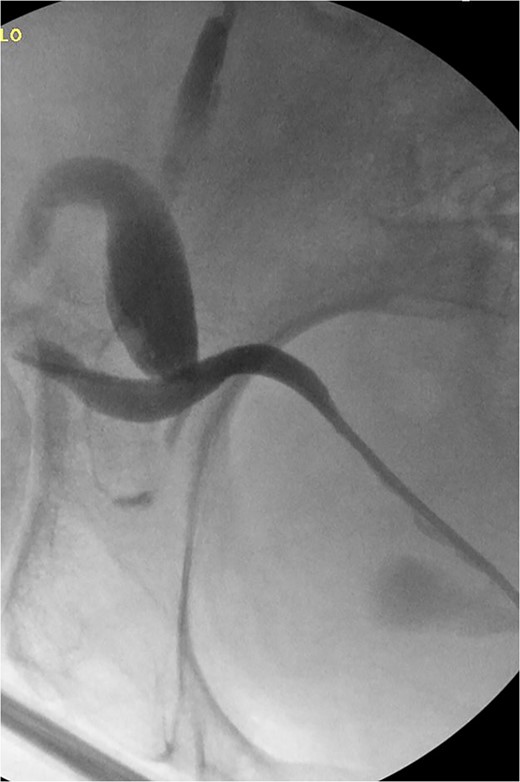

The patient was taken to the operative suite where he underwent cystoscopy, retrograde pyelogram and temporary ureteral stent placement (Fig. 2). Right inguinal exploration was performed, and the patient was found to have a large direct hernia containing abundant adipose tissue. The ureter and cord structures were identified. Adipose tissue was amputated with an energy device. The ureter was reduced into the retroperitoneum. The hernia was then repaired with modified Lichtenstein technique using macroporous polypropylene mesh. Retrograde pyelogram was repeated at completion of the hernia repair following stent removal. A serpiginous course of the ureter was noted without obstruction (Fig. 3). He was observed overnight and discharged home the following day. Post-operative course was uneventful.

Retrograde pyelogram following hernia repair with tortuous path of the ureter.